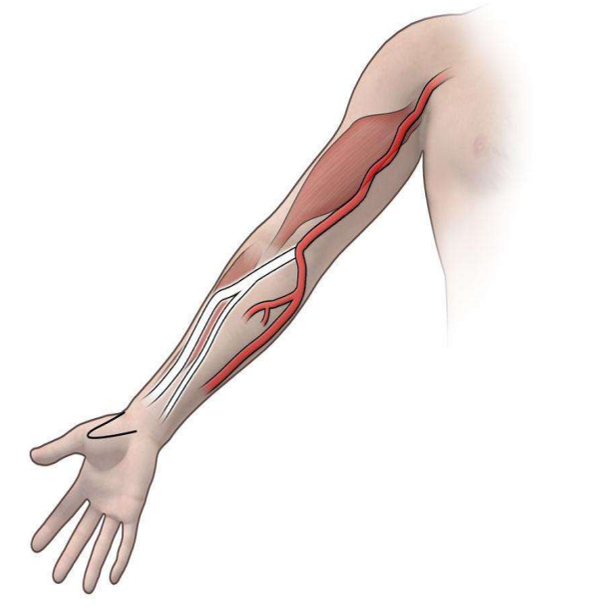

• 解剖变异是导致技术失败的最常见原因【Jelev L, 2008】3 • 远端前臂的解剖变异发生率较低【Brzezinski M, 2009】1 • 解剖变异及其对经皮穿刺入路的理论影响

桡动脉变异是临床实践中,尤其是在进行桡动脉穿刺(如冠状动脉介入治疗、动脉血气分析、有创血压监测)时,需要高度重视的解剖学问题。了解这些变异对于提高穿刺成功率、减少并发症至关重要。 以下是桡动脉主要的几种解剖变异及其临床意义: 一、 主要变异类型1. 高位桡动脉 High Origin of the Radial Artery这是最常见且最具临床意义的变异。

桡动脉变异是常见的解剖现象,高位桡动脉最为多见。这些变异是桡动脉路径操作失败和并发症的重要根源。术前细致的体格检查(尤其是高位触诊)和常规使用超声进行评估与引导,是应对桡动脉变异、实现安全高效操作的关键措施。 对于介入医生、麻醉医生、重症监护医生及护士而言,熟练掌握桡动脉变异的类型和处理策略是必备的临床技能。 |